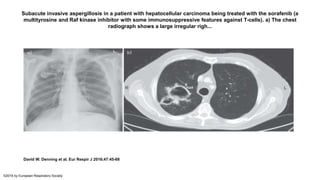

• Radiographic findings may include infiltrates, nodules, and

consolidation with or without cavitation; the most common

finding is a single area of consolidation. Unlike other forms of

CPA, pre-existing structural lung disease or cavitation is not

necessary for the development of SAIA.

Subacute invasive aspergillosis in a patient with hepatocellular carcinoma being treated with the sorafenib (a

multityrosine and Raf kinase inhibitor with some immunosuppressive features against T-cells). a) The chest

radiograph shows a large irregular righ...

David W. Denning et al. Eur Respir J 2016;47:45-68

©2016 by European Respiratory Society

Copyrights apply

• Radiographic findingsmay include infiltrates, nodules, and consolidation with or without cavitation; the most common finding is a single area of consolidation. Unlike other forms of CPA, pre-existing structural lung disease or cavitation is not necessary for the development of SAIA. • Patients with more severe underlying immunosuppression (eg, neutropenia, prolonged high-dose corticosteroid therapy) typically have Invasive Aspergillosis as opposed to SAIA.

Subacute invasive aspergillosisin a patient with hepatocellular carcinoma being treated with the sorafenib (a multityrosine and Raf kinase inhibitor with some immunosuppressive features against T-cells). a) The chest radiograph shows a large irregular righ... David W. Denning et al. Eur Respir J 2016;47:45-68 ©2016 by European Respiratory Society

• #31 Subacute invasive aspergillosis in a patient with hepatocellular carcinoma being treated with the sorafenib (a multityrosine and Raf kinase inhibitor with some immunosuppressive features against T-cells). a) The chest radiograph shows a large irregular right upper-lobe cavitary lesion that developed with multiple symptoms over 6 weeks during treatment with sorafenib. The patient presented with unresectable hepatocellular carcinoma. b) The computed tomography scan shows a dual cavity with moderately thick walls, an external irregular edge and some material within the cavity on an almost normal lung background. L: left side; R: right side.